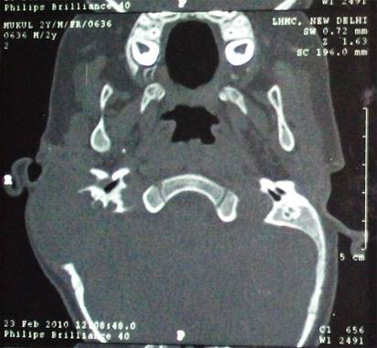

A two year old child presented to ENT outpatient department with history of right ear discharge with swelling over right post auricular region and intermittent fever with no chills and rigor for last 2 months. Child was diagnosed as chronic otitis media with mastoiditis and received 10 days course of intravenous antibiotics. In view of no improvement, patient was referred to our centre for further management. Clinical examination revealed tender right post auricle swelling of size 3 ×3 cm with soft tissue bulge visible in external auditory canal obscuring visualization of tympanic membrane. There was no facial nerve palsy, sign of sepsis or intracranial involvement. General physical examination revealed seborrheic rash over right side of temporal, parietal region of scalp and back of the patient (Fig1). Contrast enhanced computed tomography (CECT) scans showed a significant destructive bone lesion with enhancing soft tissue component of size approximately 5×4.6×3cm involving petrous ,squamous and mastoid part of right temporal bone( sparing apical petrous, inner and middle ear) causing obliteration of external auditory canal with displacement and compression of underlying brain but no evidence of intraaxial extension (Fig 2). Patient underwent biopsy from postauricle region under general anaesthesia with differential diagnosis of histiocytosis, rhabdomyosarcoma or lymphoid malignancy. Disease was found to be infiltrating temporalis muscle with bony dehiscence. Histopathology analysis revealed an sheets of polygonal cells with abundant eosinophilic cytoplasm, lobulated indented nuclei showing grooving prominent admixture of eosinophils with few histiocytic giant cells suggestive of Langerhans cell histiocytosis(Fig 3). Positive immunohistochemical staining for S-100 protein confirmed the diagnosis. Complete blood count reveal raised ESR (84mm/hr). Liver function test, coagulation studies and urine osmolarity test were normal. Skeletal survey and bone marrow examination ruled out multi organ involvement.

Fig.2: CECT Temporal Bone (Axial Cut) showing destructive bony lesion with enhancing soft tissue component of size involving petrous, squamous and mastoid part of right temporal bone.